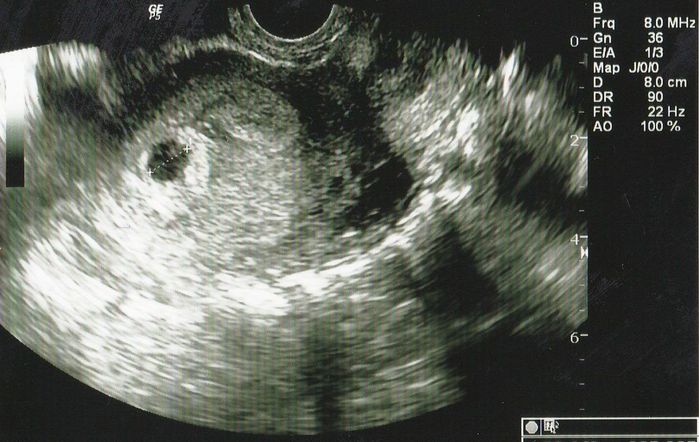

妊娠4週目のエコー写真 直径9mmの小さな、小さな胎嚢を確認

妊娠検査薬で陽性反応が出たので、夫が休みの週末を待って2人で病院へ行きました。左上部に見える黒い丸が妊娠した目印となる胎嚢です。「やっと妊娠できた」という、うれしさはもちろんありましたが、小さな命が自分のおなかの中にあるということが信じられず、他人事のような不思議な感覚でした。